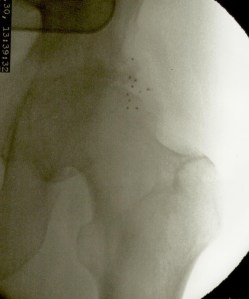

Más abajo se observarán unas imágenes de casos de implantes de oro en cadera